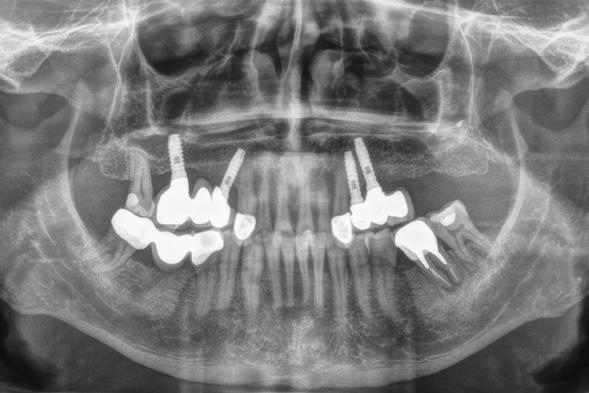

Explantación atraumática y recambio de implantes mal posicionados y afectados por periimplantitis sumado a la utilización de implantes estrechos y cortos. Enfoque mínimamente invasivo de un caso de atrofia ósea moderada

42 | INVESTIGACIÓN CLÍNICA